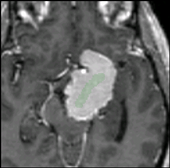

Caption 1

Caption 2

Caption 3

Caption 4